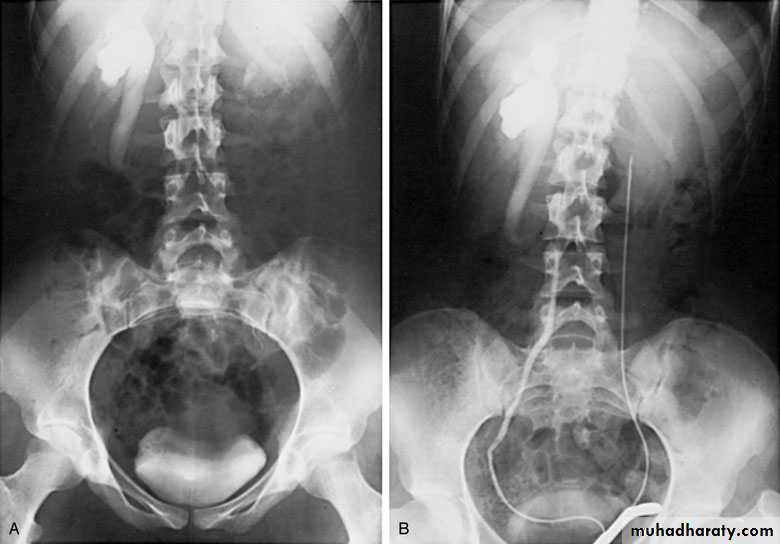

IVU, cystoscopy, cystogram

The ‘adder head’ on excretory urography

is typical.

Cobra (Adder) head appearance of ureterocele

Ureterocele involving single system Ureterocele involving duplicated ureter

Postcaval (Retrocaval) ureter (Preureteral Vena Cava )

The right ureter pass behind the inferior vena cavaThis might causes obstruction

Diagnosis: IVU